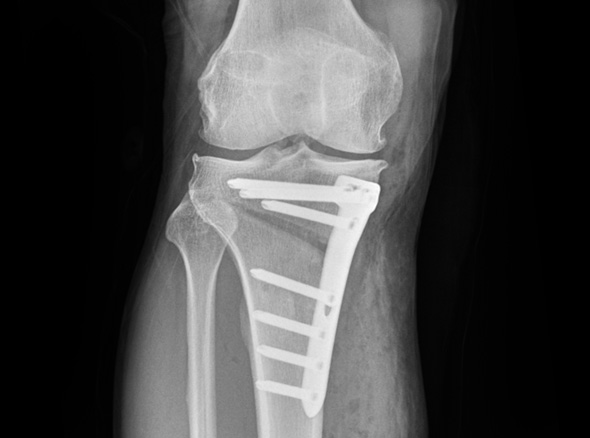

이동시키는 ‘무릎관절 교정 절골술’을 시행합니다.

* 환자에게 받은 소중한 자료입니다.

※ 금속판과 나사는 수술 후 약 1~2년 후 제거합니다.

관절내시경을 이용하여 연골재생이나 연골판에 필요한 치료를 시행한 후 경골(무릎 아래 뼈)의 근위부의

계획한 위치까지 절골을 시행한 후 뼈의 탄성을 이용하여 벌립니다. 그리고 금속판과 나사로 고정하여

수술 전 계획했던 X자형 또는 1자형 다리를 만들고 빈 공간에 뼈를 이식하여 골유합을 유도합니다.